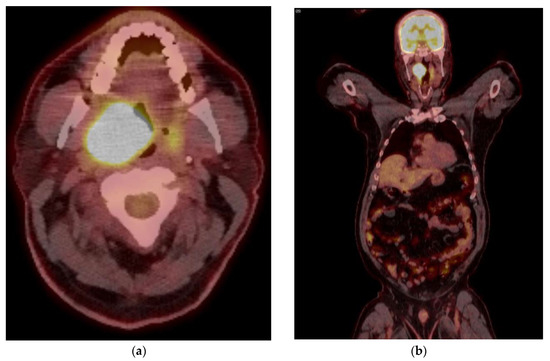

5. Imaging of Oropharyngeal Cancers

8.1. Initial Staging